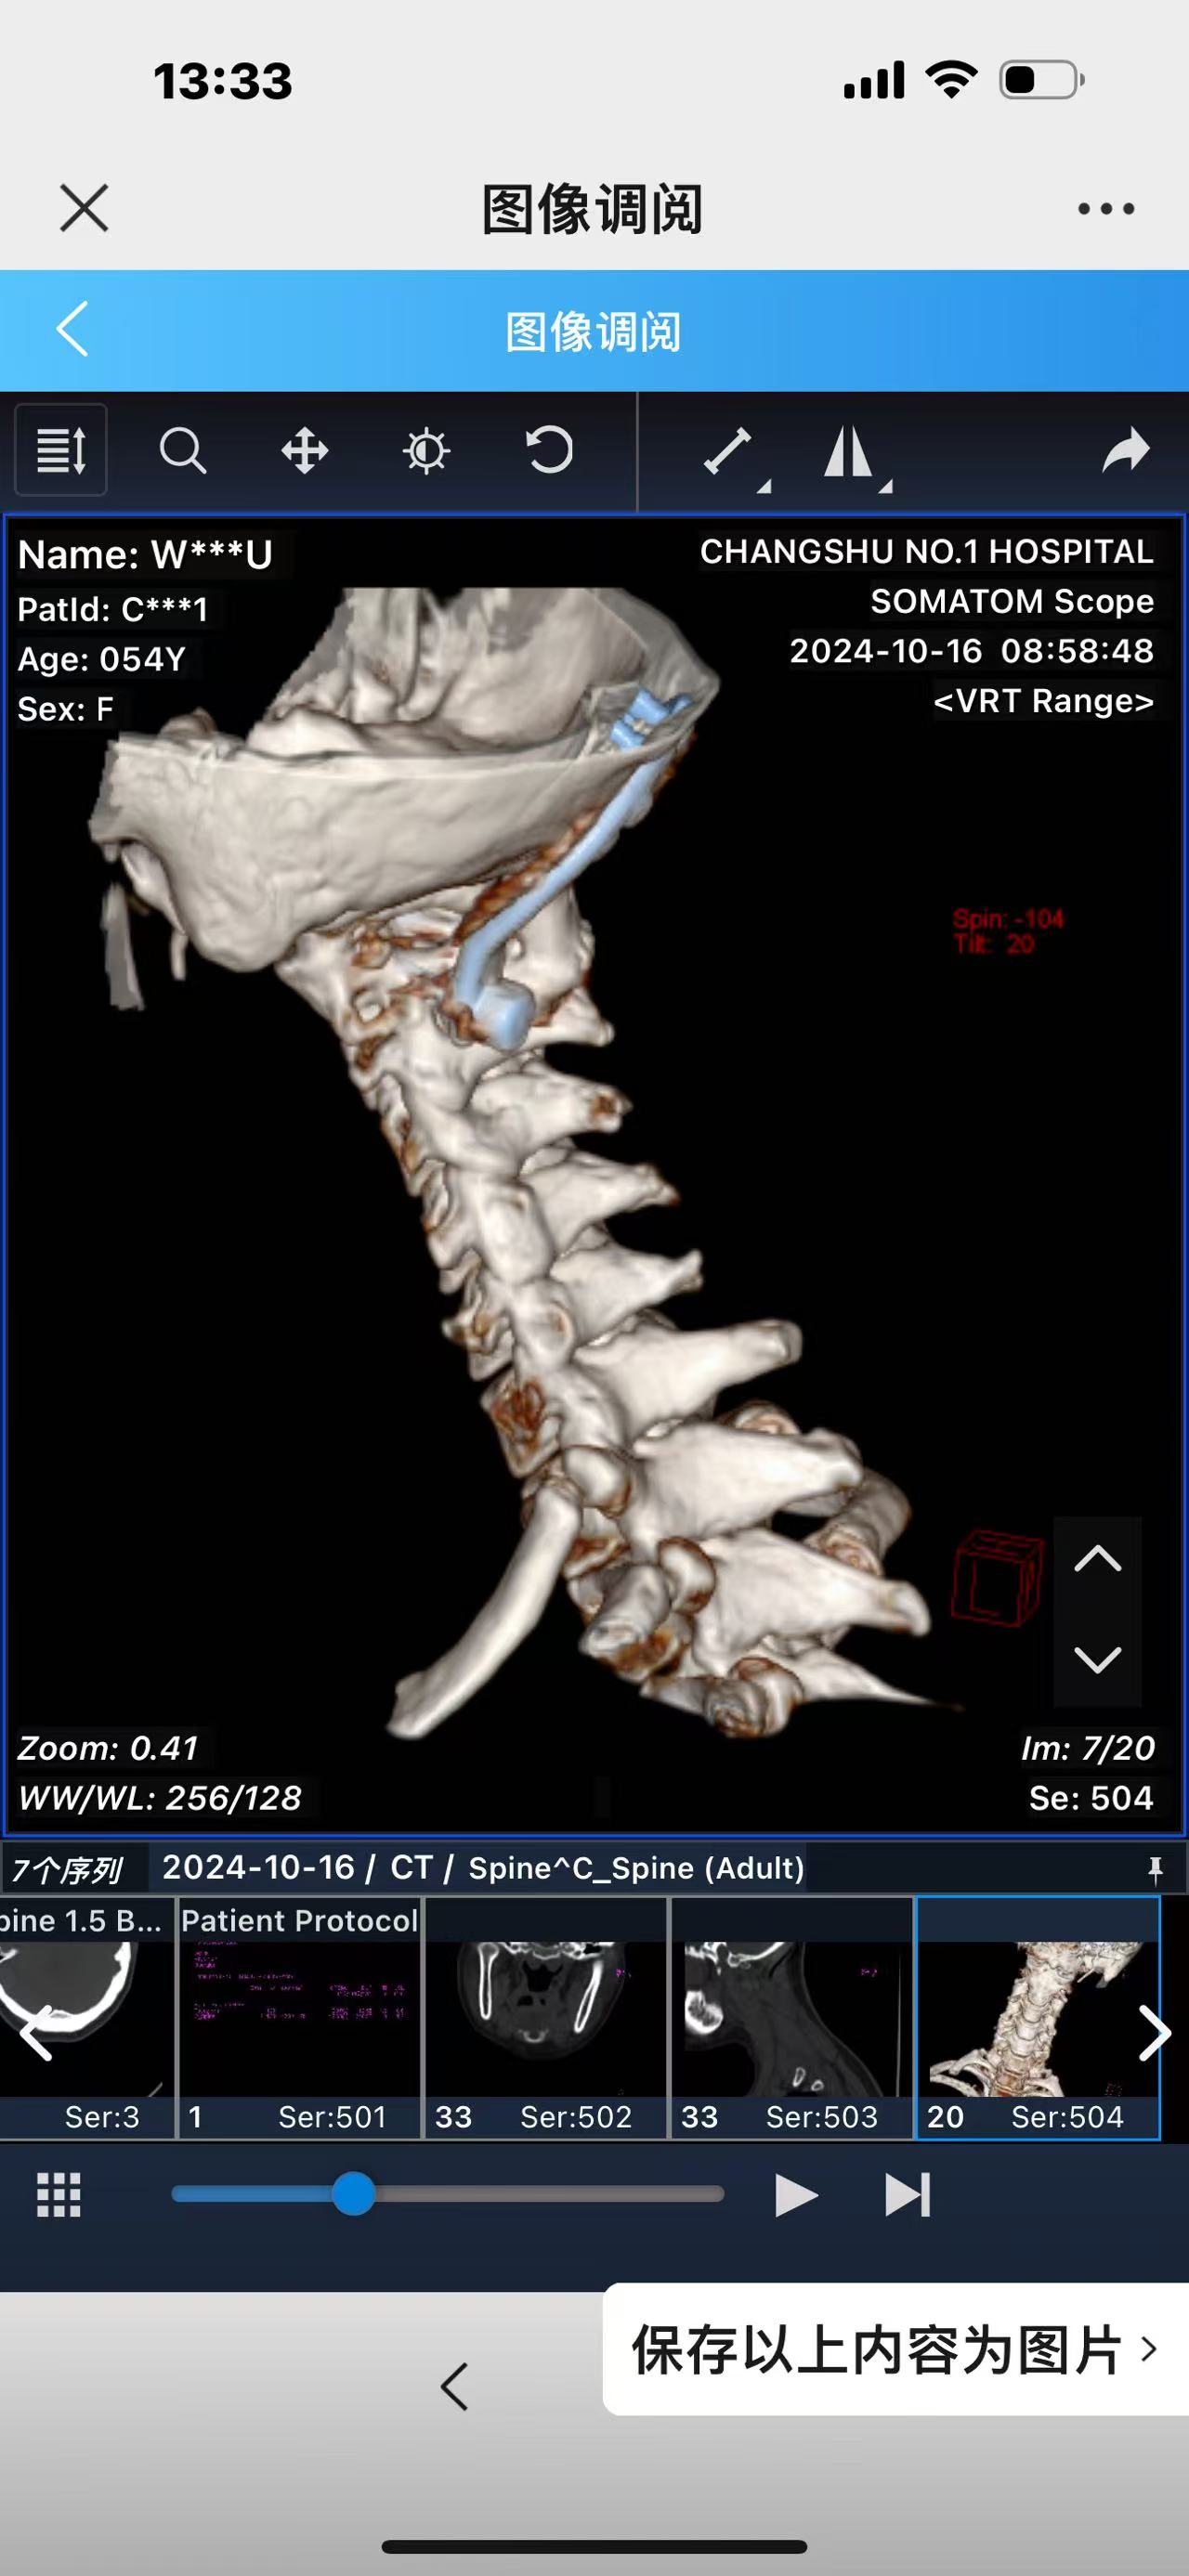

• 诊断:寰枢椎脱位,颅底凹陷

• 影像: